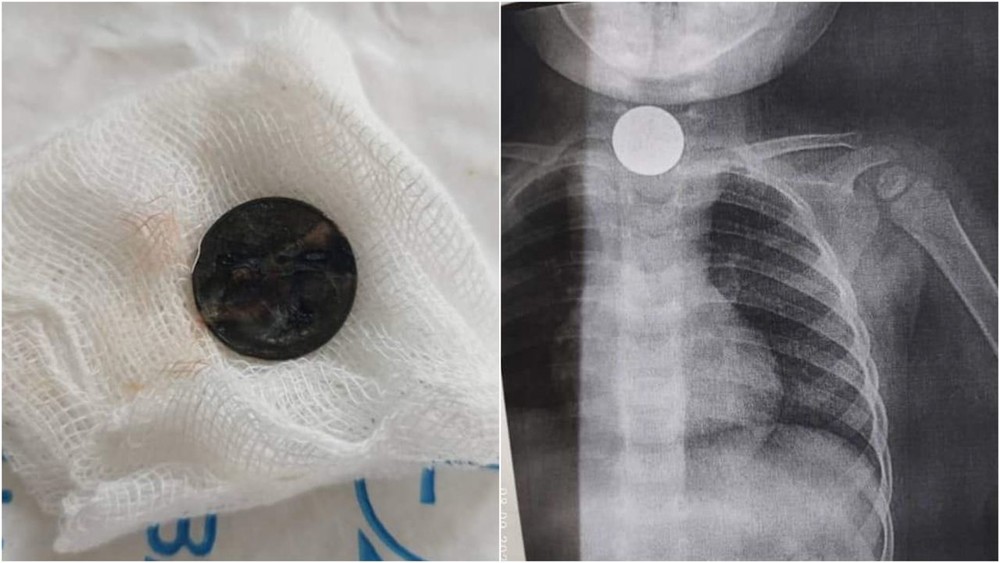

«2 ай бою жөтөлүп жүрө берген»: Ошто тыйын сымал затты жутуп алган 2 жаштагы кыз куткарылды